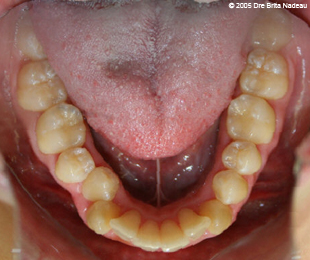

Marie-Hélène Cyr - Lower occlusal view - Before orthodontic treatments and orthognathic surgeries (November 24, 2005)

November 24, 2005 - The crowding of my teeth is also visible on this lower occlusal view.